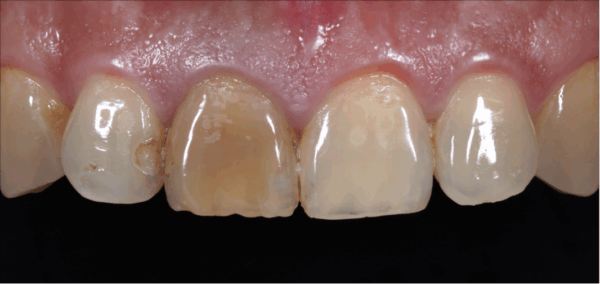

門牙斷掉怎麼辦?牙醫解析門斷裂的原因、常見治療方式與真實案例,包括美學樹脂、陶瓷貼片與全瓷冠修復。

門牙補過變黑?美學樹脂讓你不磨牙也能改善|吉士牙醫

門牙補過反覆變黑?不一定要做貼片或牙套。美學樹脂可以在保留齒質的前提下改善黑邊與外觀。本文用真實案例帶你了解判斷邏輯、適合對象與治療流程。